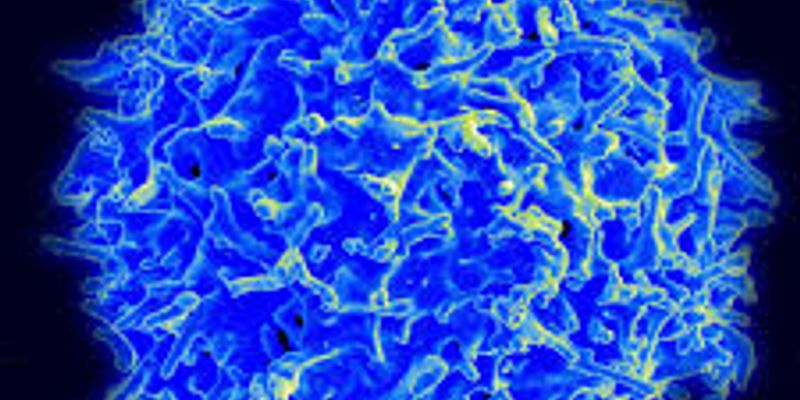

T-Cells

T-Cells: A type of white blood cell that plays an important role in the immune system. They are produced by the thymus gland and help the body fight off viruses, bacteria, and parasites.